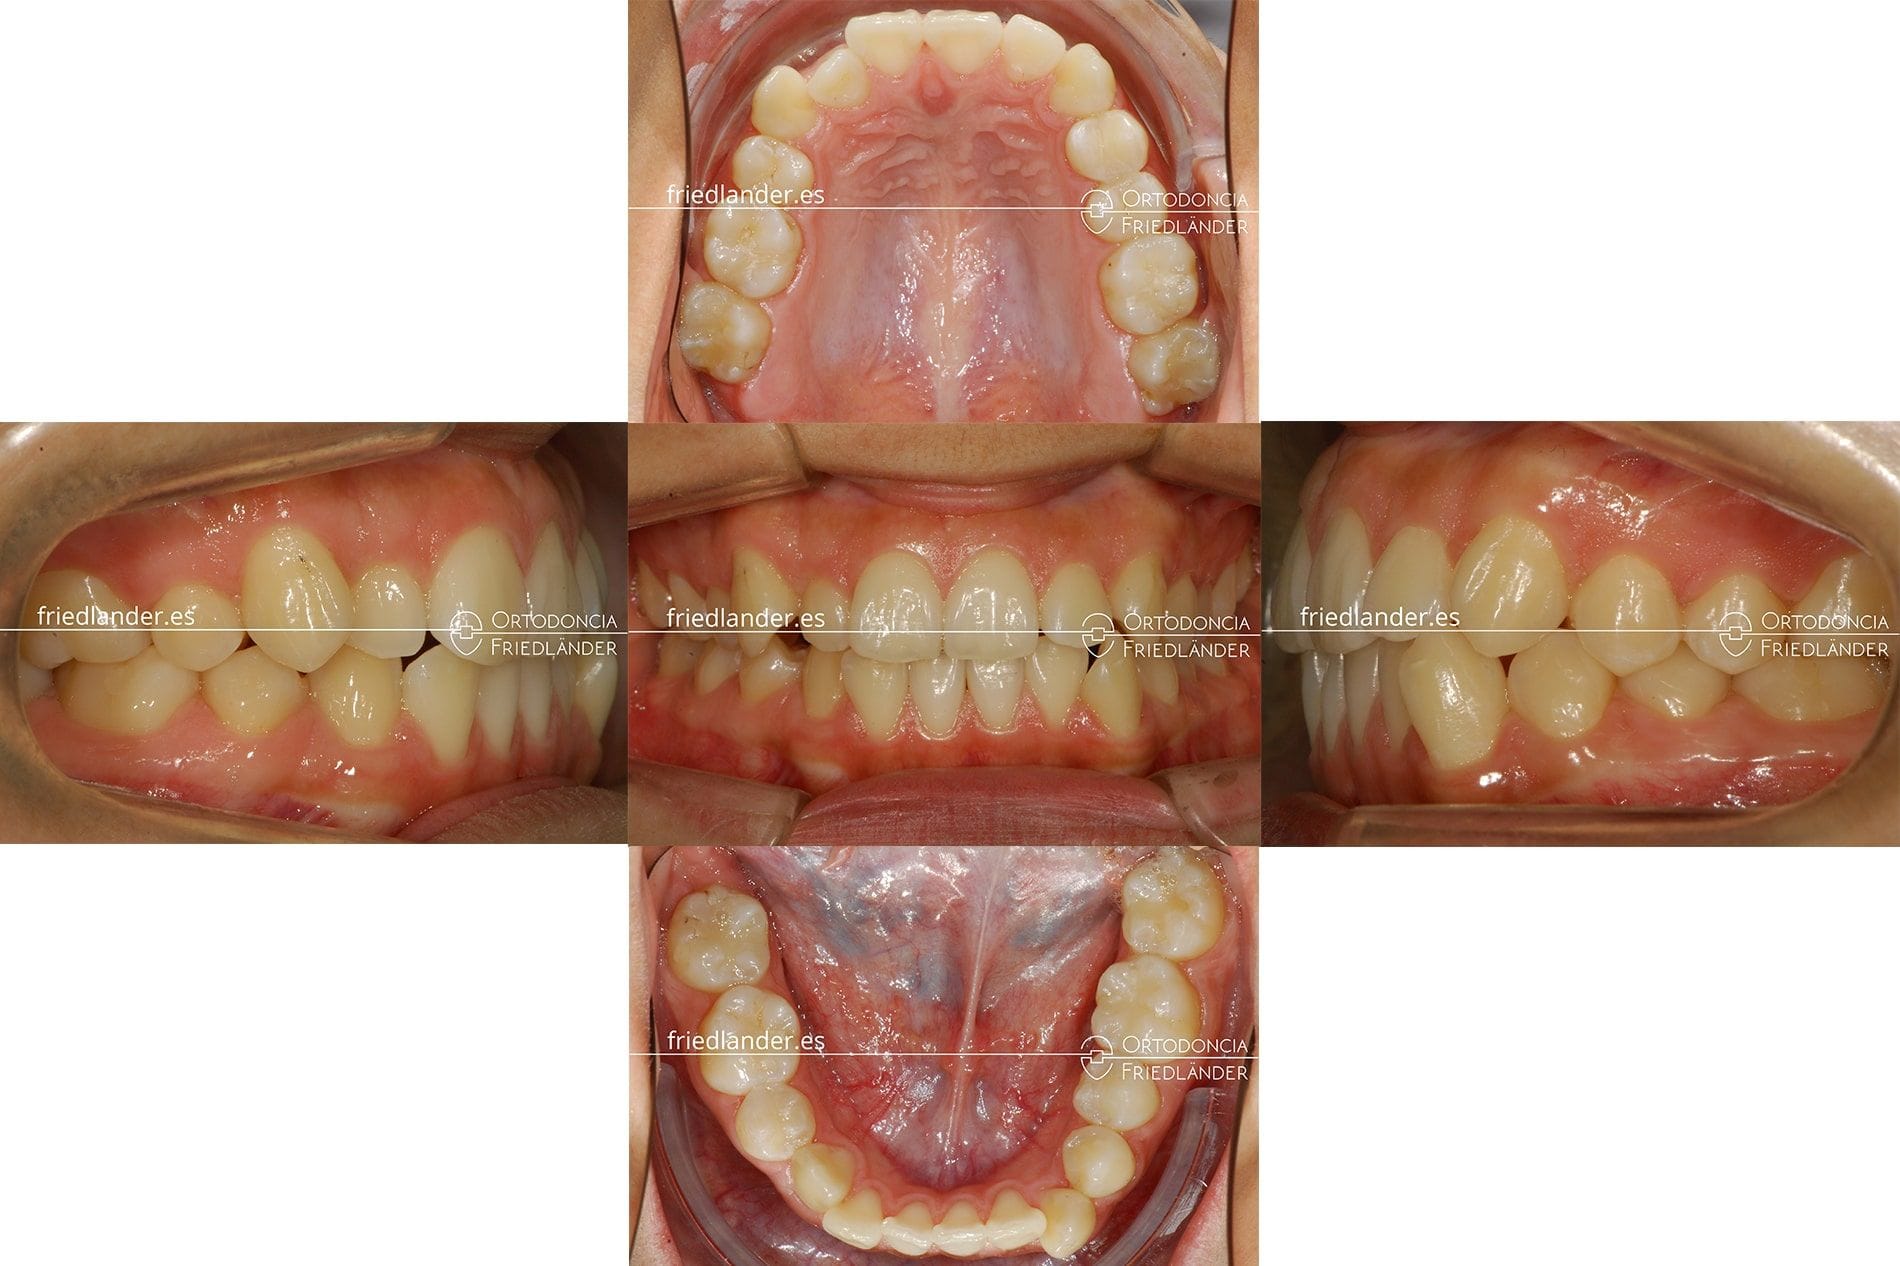

Paciente de 25 años acude a su primera visita en nuestra clínica en Barcelona. El principal motivo de consulta de la paciente es la desviación de su línea media dental.

La paciente nos comentó que su dentista le extrajo estos premolares porque faltaba espacio en la arcada dental para que todos los dientes pudieran erupcionar. Evidentemente, este tratamiento no era el indicado ya que genera otros problemas como la desviación de las líneas medias y crea una asimetría en la sonrisa.

Imagen de la arcada superior donde se puede ver el desplazamiento de la línea media al centra de la arcada.